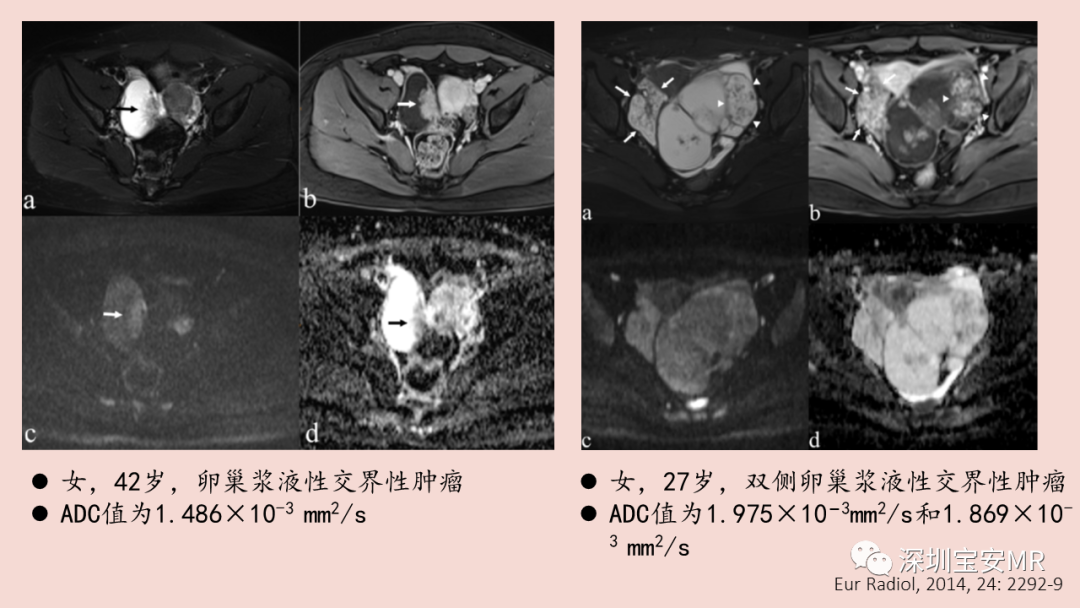

图片